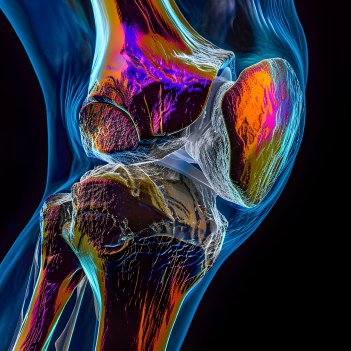

Well, take a look at this picture:

This is the most dangerous acid in the world.

It’s called “fluoroantimonic acid” and it can burn through almost anything including glass, ceramic materials, and even some metals.

And as scary as this may sound, YOU actually have a similar acid building up and bubbling inside your joints…

And when this acid builds up…

It eats away at your joints just like that acid eating through sheet metal…

And over time this literally works to DISSOLVE the cartilage and other cushioning tissues from the inside out.

As a result, your joints suffer and you experience aches, stiffness, and burning…